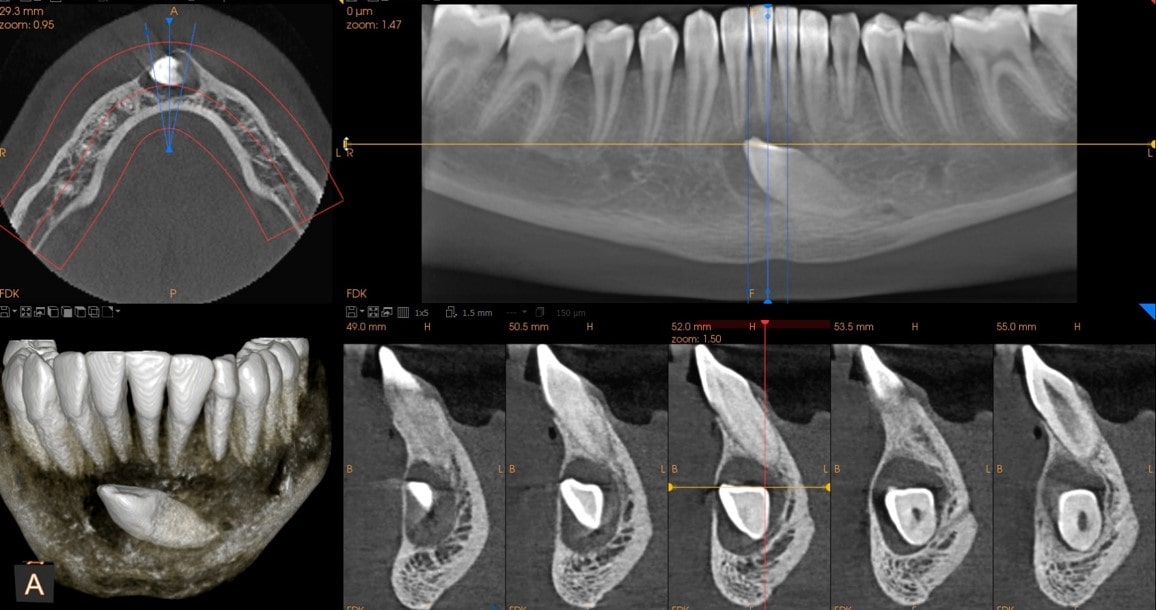

Planowanie implantów

tomografia szczęki w Białymstoku

tomografia szczęki Białystok

Endodoncja (leczenie kanałowe)

zdjęcie tomograficzne szczęki